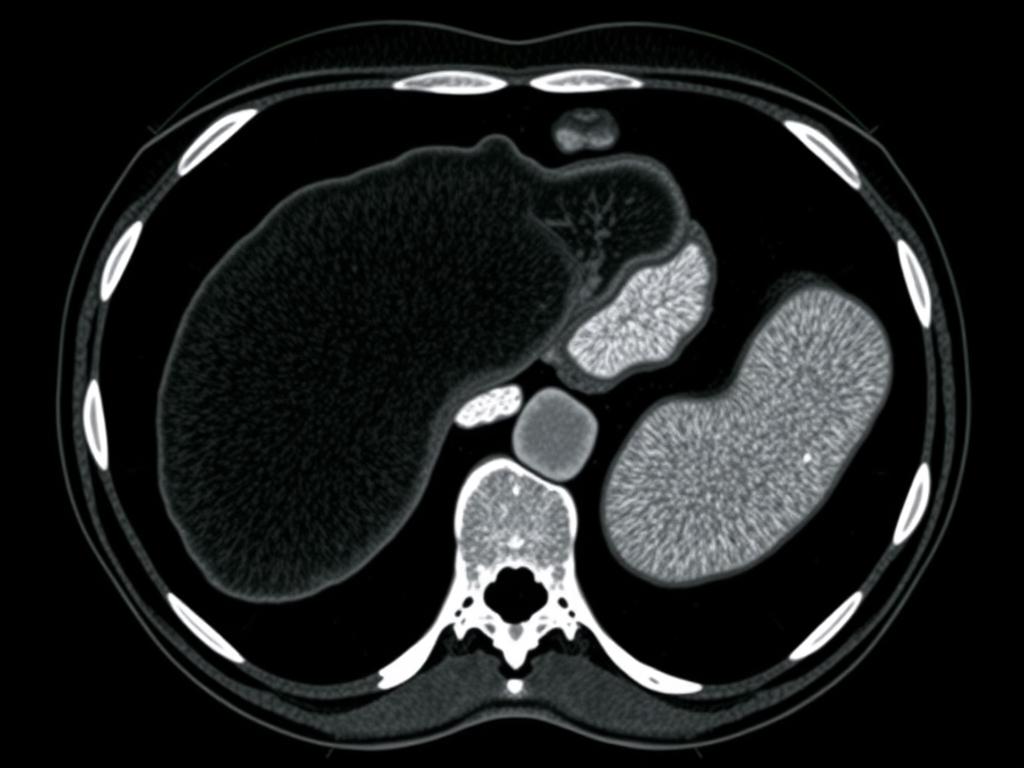

Tomografia Computadorizada

Fornece imagens mais detalhadas e pode quantificar com maior precisão o grau de infiltração gordurosa, além de identificar outras alterações hepáticas.